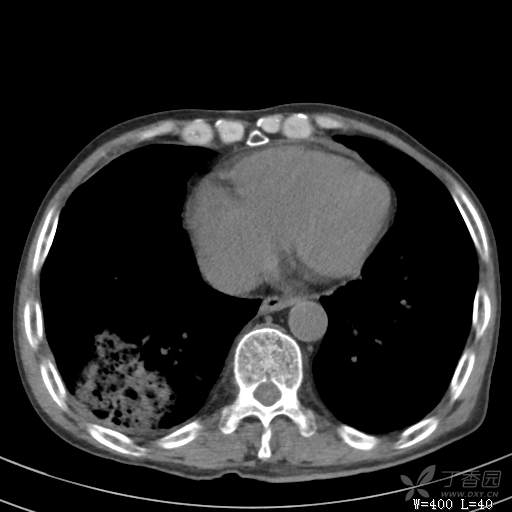

简要病史:主因发热伴腰背部疼痛2小时于2018-06-27,09:30 入院。患者无高血压,冠心病、糖尿病病史,无慢性咳喘史,不吸烟。否认食物药物过敏史。患者于入院前2小时出现发热,体温37.5℃,无咳嗽,咳痰,伴右侧腰背部疼痛,伴呕吐2次,呕吐物为黄绿色胆汁,大便2次,为稀便,无咯血,无胸闷、憋气,无鼻塞、流涕,无尿频、尿急、尿痛,就诊于我院,我院急诊查:上腹部CT:右肾结石,右下肺感染性疾病可考虑,血常规WBC13.54*109/L,GR%45.8%,急诊以“发热待查:肺感染?”收入院。

辅助检查:上腹部CT:右肾结石,右下肺感染性疾病可考虑,血常规:WBC13.54*109/L,GR%45.8%,。心肌酶示:谷草转氨酶12U/L,乳酸脱氢酶328U/L,肌酸激酶20U/L,肌酸激酶同工酶7U/L,α-羟丁酸脱氢酶277U/L,查凝血常规示:凝血酶原时间12.5秒,国际标准化比值1.07,活化部分凝血酶原时间32.6秒,纤维蛋白原浓度1.77g/L,凝血酶时间15.6秒。

临床诊断:1.腰背部疼痛原因待查:1.肺炎?2.泌尿系结石?。

治疗经过:抗感染及止痛对症处理。治疗效果不好,患者腰痛是由什么引起的?